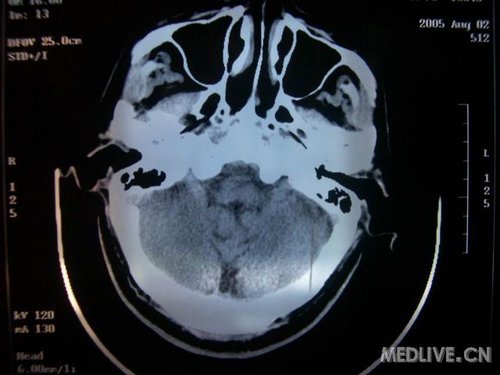

此次入院时的片子: